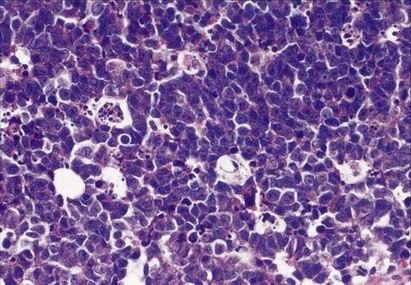

Diferenciální diagnostika malobuněčných tumorů

V klasické histologii podobné až nerozpoznatelné

K diferenciální diagnóze nezbytné imunohistochemické (IHC) vyšetření větším počtem protilátek

Bez IHC je přesná diagnóza nejistá